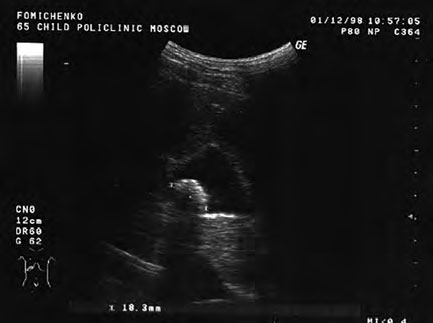

Перед началом курса лазеротерапии больная предъявляла жалобы на общее нарушение самочувствия, чувство тяжести и постоянные тянущие боли в правом подреберье, диспепсические расстройства. Больная на протяжении длительного времени пользовалась болеутоляющими, спазмолитическими и ферментными препаратами. Проведенное ультразвуковое исследование выявило деформацию и эхо-признаки воспаления стенки желчного пузыря, наличие конкремента в желчном пузыре, расширение печеночных желчных протоков. Неподвижность конкремента при смене положений тела больной свидетельствовало о его спаянности со стенкой желчного пузыря. Максимальный размер конкремента в исходном (до начала курса лазеротерапии) ультразвуковом исследовании составил 18,3 мм (рис. 27).

Рис. 27. Исходные (до начала курса лазеротерапии) данные ультразвукового исследования желчного пузыря больной Т. Ф-ко